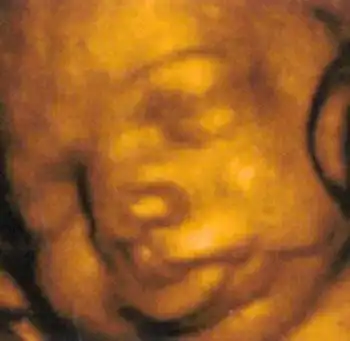

Создатель этой системы профессор Стюарт Кэмпбелл, один из ведущих акушеров Соединенного Королевства, стал знаменитостью в мире медицины благодаря снимкам, на которых зародыш улыбается (раньше считалось, что эта способность появляется лишь после рождения)...

Специалисты признают, что эти снимки, прежде всего помогающие оценить правильность развития плода, завораживают...

"Книги Кэмпбелла, которые он создает для молодых родителей, не просто сборник фотографий неродившегося малыша, это целая вселенная," - утверждают они.